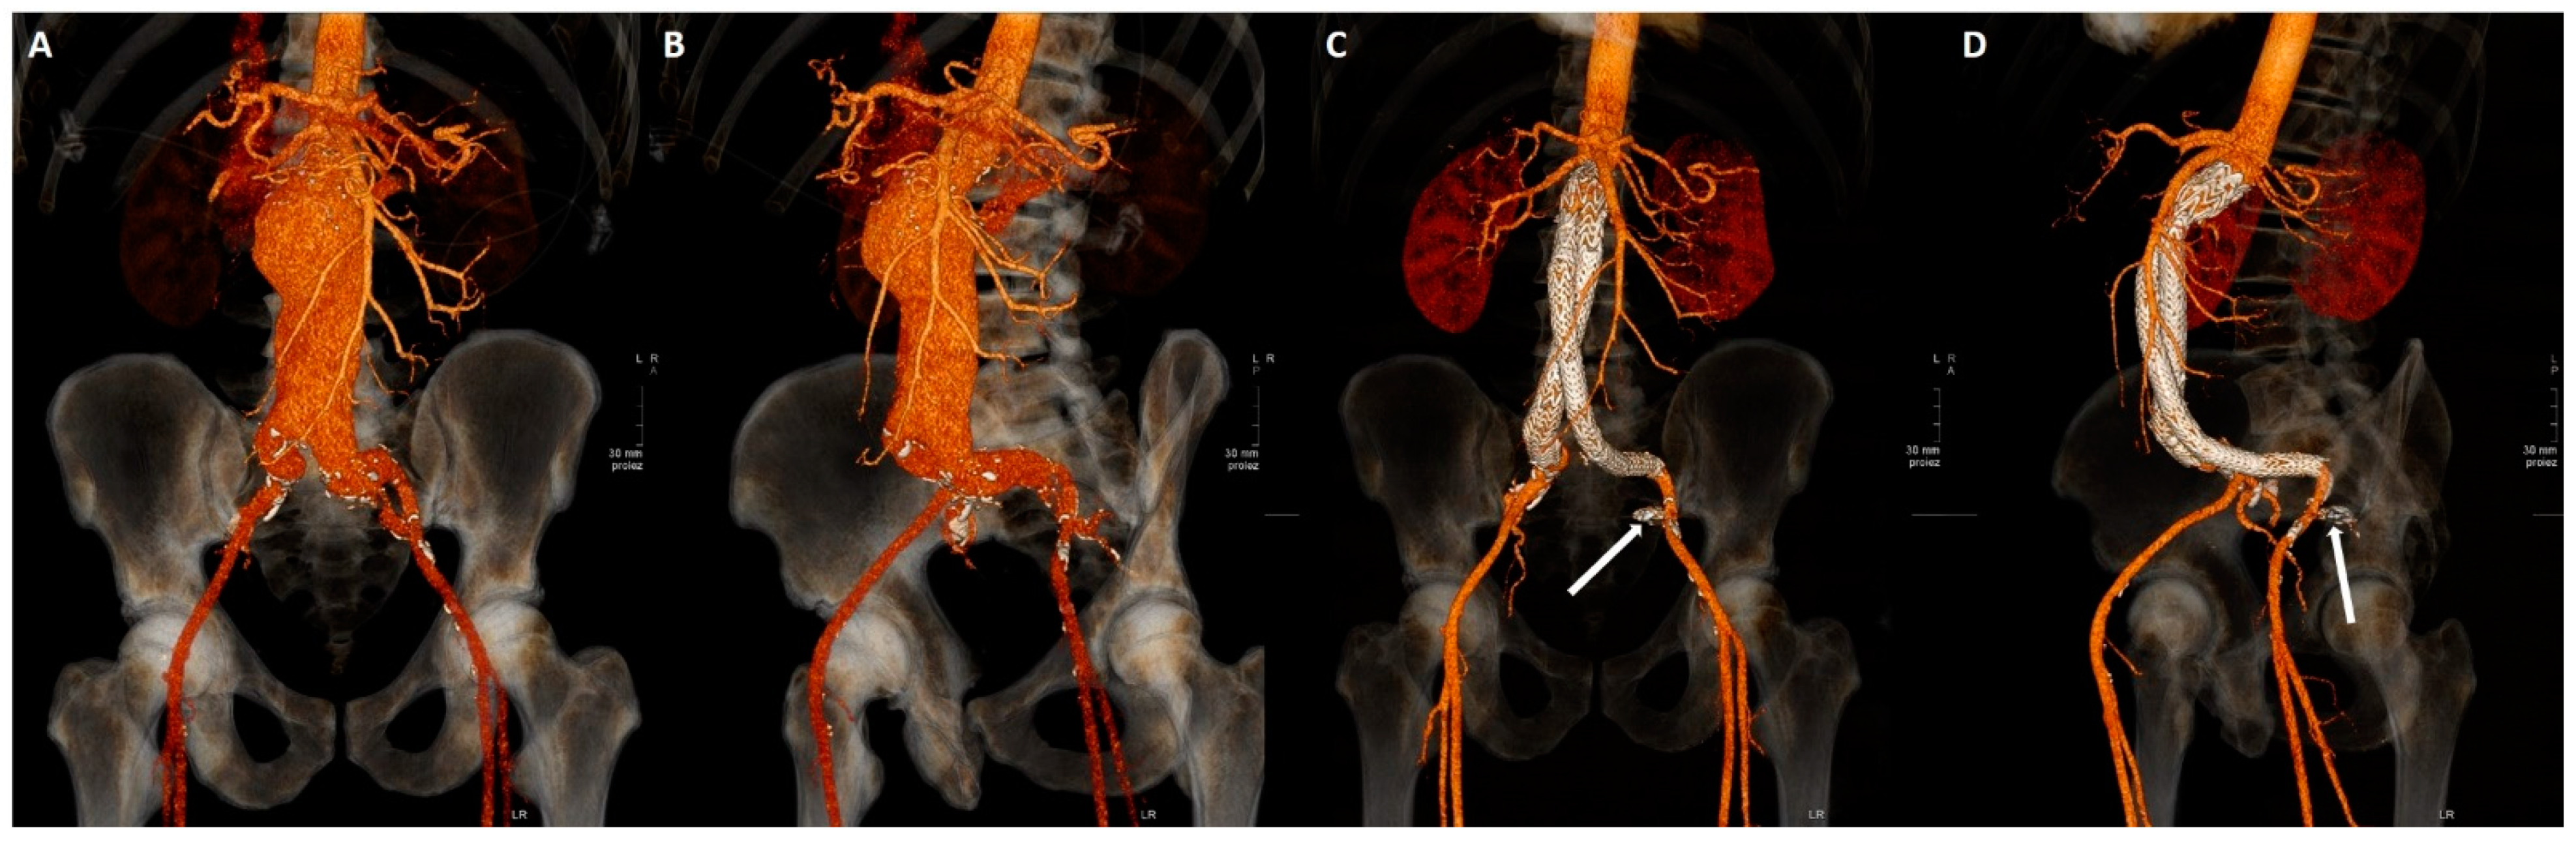

Patients underwent clinical, contrast enhanced US (CEUS) and CT angiography (CTA) follow-up at demission time and at 1, 3, 6, 12 months from procedure, then annually. Clinical evaluation was performed at all checkpoints, CEUS and CTA were alternated starting with CEUS at 1 month. If CEUS was positive for EL, CTA was immediately performed (Figure 2).

Figure 2.

(A–D). Volume rendering reconstructions from CTA before (A,B) and after (C,D) EVAR procedure with left ipogastrigc embolization with coils (arrow).